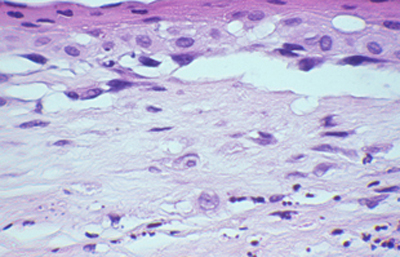

Cuando el examen patológico se realiza en cortes de tejido corneal procesados en parafina, (biopsias y discos de córnea de queratoplastias) las coloraciones que empleamos usualmente son la coloración de Hematoxilina-Eosina (Figura 49), el Blanco de Calcofluor. (Figura 50), la de PAS (Figura 51 y 52). De nuevo, la consideración de que una infección corneal puede ser causada por Acantamoebas es la condición indispensable en el diagnóstico diferencial para llegar a su diagnóstico

Acanthamoeba H-E, Original x160

Fig. 49 H-E, Original x160